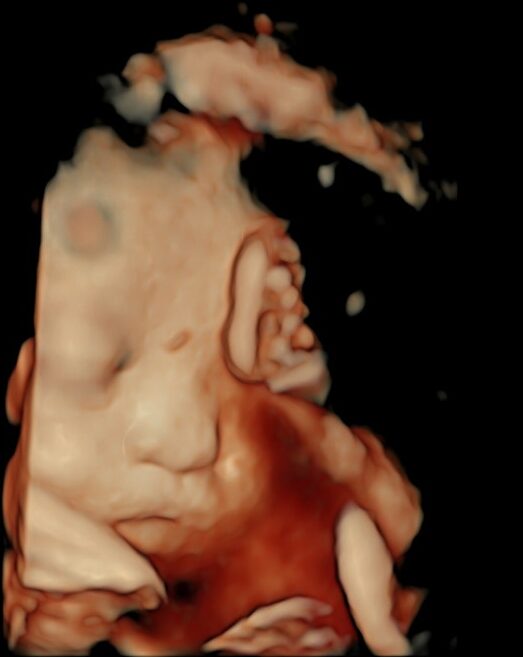

条件が良ければ、こんな感じで赤ちゃんをみることができます(写真は、お母さんにホームページに載せることを許可していただいています)。

赤ちゃんの協力も必要なので、残念ながらいつもこのようにみえるわけではありまんが、

お腹の中で元気に育っている姿をみると、幸せのおすそ分けをしてもらっているような気分になります。

飲んだり、呼吸したり、体を動かしたり、産まれたあとにしっかりと生きていくために頑張って練習しています。